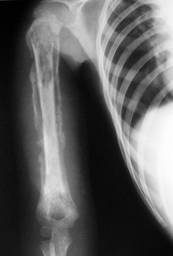

OSTEOGENEZA IMPERFECTĂ PRECOCE fragilitate anormala a oaselor cu fracturi spontane care apar dinaintea nasterii, calota craniana foarte subtire cu consistenta inegala (mar putred), fontanele largi, prognostic rau (rareori ajung la 20 de ani); este ereditara recesiva.

OSTEOGENEZA IMPERFECTA TARDA apare dupa primul an mai ales la membrele inferioare, talia este normala, oasele sunt subtiri, demineralizate, se fractureaza usor chiar la miscari normale. Prognosticul este bun; se vindeca între 10 si 20 de ani. Se transmite ereditar dominant si recesiv.